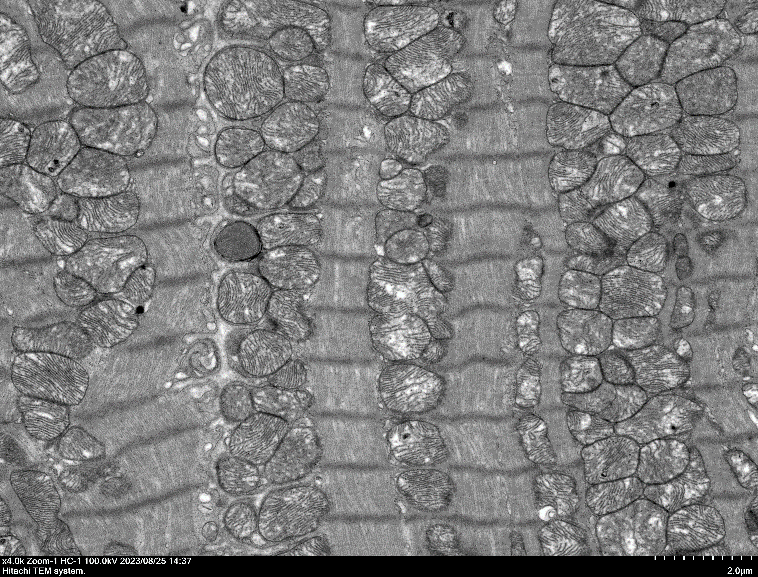

心肌超薄切片 X4000